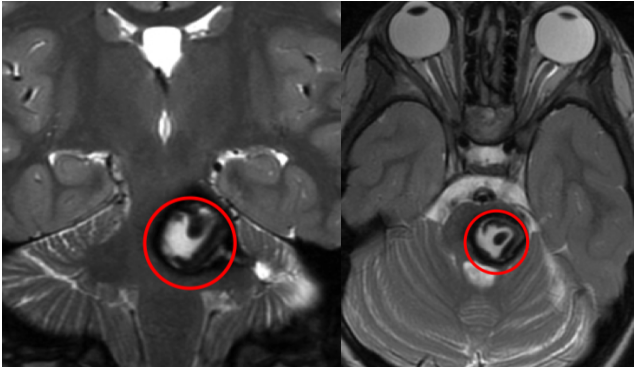

红色为术前,绿色为术后即刻颅脑MR影像,显示病变已全切,无脑水肿、出血等并发症,瘤腔内高信号灶为止血材料。